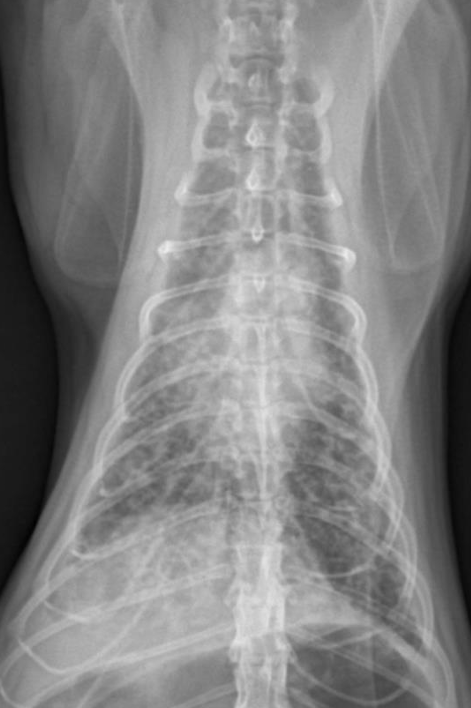

6️⃣ Bacterial Pneumonia (세균성 폐렴)

- 구강 인두에서 음식물 떨어져서 생길 때도 흔함.

- 세균이 airway를 타고 들어가 폐에 감염 → 전엽, 중엽에서 많이 발생.

- 고양이에서는 혈액성 origin의 폐렴이 많다. → 후엽, 전체적(diffuse) 패턴

- air bronchogram(=alveolar pattern), bronchial pattern, lobar sign 보임

진단

- CBC : neutrophilic leukocytosis with left shift, neutropenia with degenerative left shift. stress leukogram

- Alveolar pattern : 가장 흔한 패턴 + consolidation

- Bronchial & interstitial markings : 종종 나타남.

- interstitial pattern alone : early or mild dz / 혈행성 감염.

- bronchial pattern alone : bronchial infection.